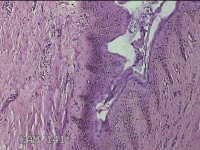

右下腹部切口结节

性别

女

年龄

27岁

临床诊断

皮下结节

一般病史

发现右下腹部切口结节10余年。

标本名称

大体所见

灰白暗红色带皮肤样结节2.3x1.3x0.8cm一个。表面糜烂,切面灰白色,质硬。

需要侵袭性纤维瘤病和纤维瘢痕鉴别一下